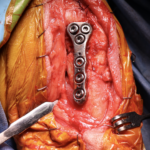

CBLO #248

性の前十字靭帯断裂の中型犬にCBLOで安定化を実施しました。慢性経過のためミディアルバトレスが分厚くなって触知することが可能です。また関節内を探査すると、内側半月板の尾側領域はダブルバケットハンドルという状態で亀裂が2ヶ所確認されました。しばらくは安静が必要です。